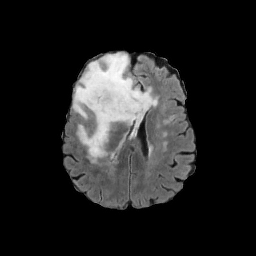

MRI

Refer to caption

Target\mathrm{Target}

Zoomed

StolenEPD{\mathrm{Stolen}}^{\mathrm{D}}_{\mathrm{EP}}

StolenEPD1{\mathrm{Stolen}}^{\mathrm{D1}}_{\mathrm{EP}}

StolenITD{\mathrm{Stolen}}^{\mathrm{D}}_{\mathrm{IT}}

StolenITD1{\mathrm{Stolen}}^{\mathrm{D1}}_{\mathrm{IT}}

Figure 7: Lossy image reconstructions on CT (row 1, 2) and MRI (row 3, 4) images, where the row 2, 4 provide a zoomed-in view of the bounding box region of the row 1, 3. The leftmost column represents the target images, while the subsequent four columns show the stolen images reconstructed by the decoder D or D1 in two scenarios.

A visual comparison between target and stolen images is available in Fig. 7. We observe that the stolen images from IT Scenario closely resemble the input ones, particularly in the tumor regions, whereas stolen images from EP Scenario exhibit blurring artifacts in finer details. In both cases, the stolen images reconstructed by D1D1 demonstrate a comparable quality to those reconstructed by DD, thus further confirming the effectiveness of the reduced decoder D1D1.